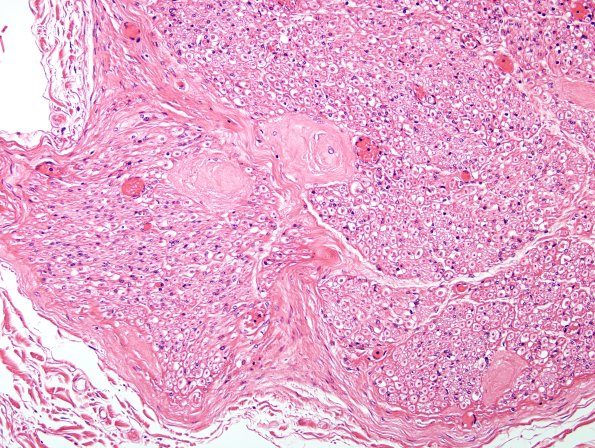

Washington University Experience | PERIPHERAL NEUROPATHY | 1 NORMAL NERVE ANATOMY | 8 Renaut bodies | 6A3 Renaut body (CIDP, Case 6) L Brachial Plexus H&E 3

This nerve was biopsied with a suspicion for CIDP but showed multiple rather dense RB instead. (H&E)